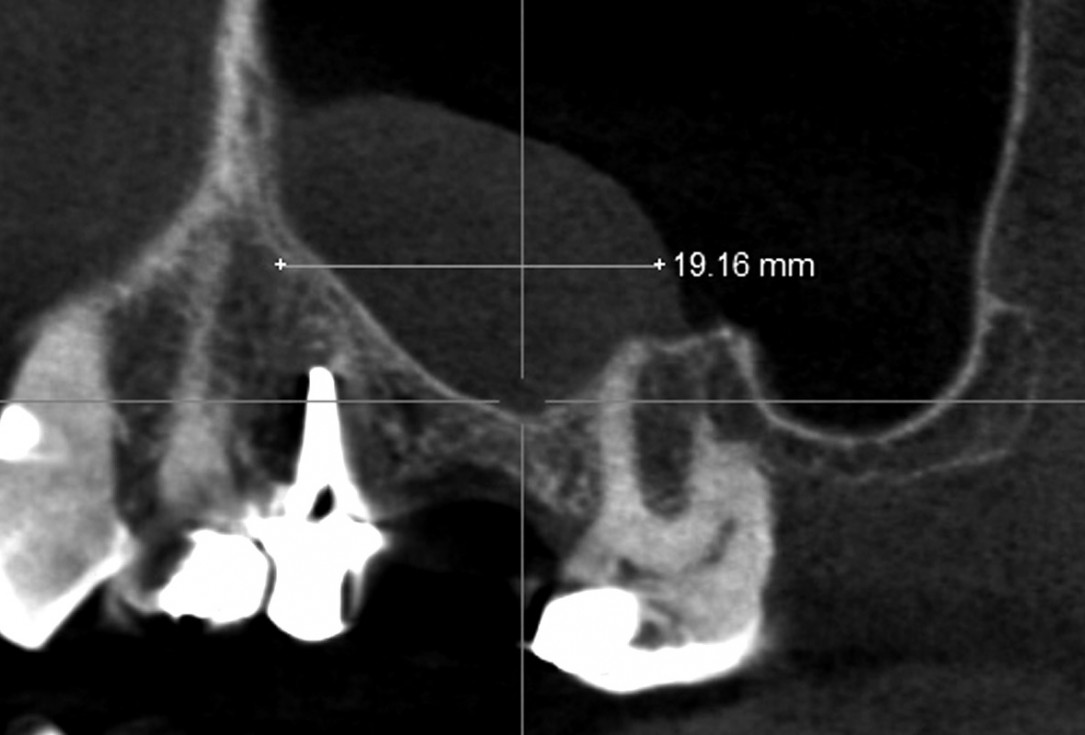

02/35 - CBCT shows maxillary sinus cystMaxillary sinus cyst removal using the Crocodile Technique and subsequent lateral sinus lift - Dres. C. Scognamiglio and A. Perucchi